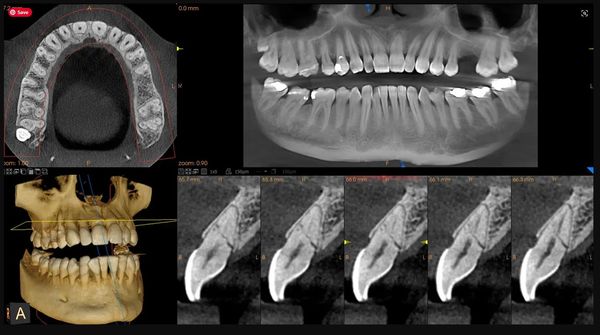

A Cone Beam CT (CBCT) scan, also called a 3D dental x-ray, is an advanced imaging technology that provides a three-dimensional view of your teeth, jaws, sinuses, and surrounding structures. Unlike traditional 2D x-rays, CBCT captures the full anatomy in high detail, giving your dentist or oral surgeon the most accurate information for diagnosis and treatment planning.

CBCT scans are especially useful for:

• Comprehensive, three-dimensional view: Provides a complete picture of your oral anatomy, revealing details that 2D x-rays may miss.

• Precise treatment planning: Helps your dentist place implants or perform surgery with greater accuracy, improving outcomes and reducing risks.

• Low radiation for 3D imaging: Modern CBCT units are designed to minimize exposure while delivering detailed images.

• Quick and non-invasive: The scan typically takes less than a minute, and you remain seated or standing during the process.

• Improves communication: 3D images allow your dentist to explain findings clearly, helping you understand your treatment options.